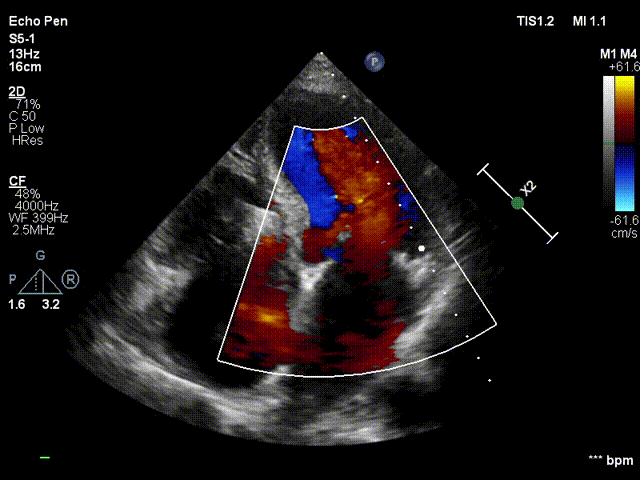

术前TEE:食道中段view提示三尖瓣重度反流

3DTEE显示双房及右室扩大(RA52mm×50mm;RV31mm);左房及左心耳未见附壁血栓;左室下壁基底段运动减弱;三尖瓣环左右径38mm,三尖瓣前叶长度24.5mm,后叶 长度25.7mm,三尖瓣隔叶长度15.7mm,三尖瓣后隔gap3.1mm;前隔gap2.3mm,三尖瓣 TAPSE16mm;余各瓣膜回声纤细柔软,开放幅度正常;未见心包积液。2、彩色及频谱多普勒显示:收缩期三尖瓣口反流束主要来源于前隔交界,前隔交界反流束缩流颈宽度6.7mm,后隔交界反流束缩流颈宽度5.8mm;舒张期三尖瓣口平均跨瓣 压差1mmHg;收缩期二尖瓣口可见微量反流信号;舒张期主动脉瓣口反流束缩流颈宽 度3.0mm;PAPs35mmHg。